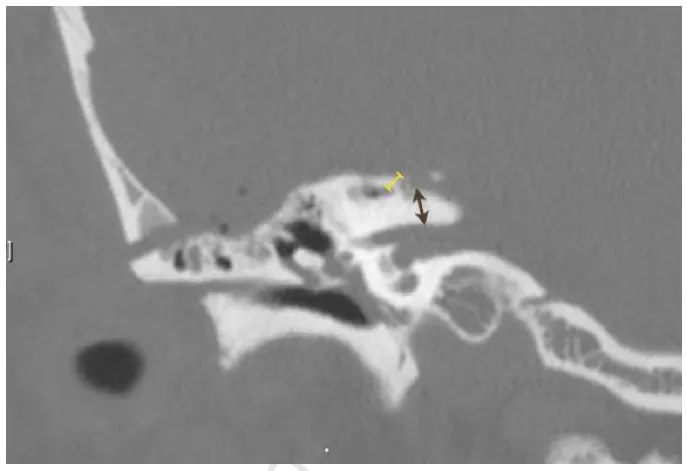

术后冠状位视图标注——棕色为钻磨终点与内听道间距(N7),黄色为钻磨起点与上半规管间距(N8)

黑点指示钻磨起始点即Kawase三角后部,箭头指示岩大神经作为Kawase三角外侧解剖标志